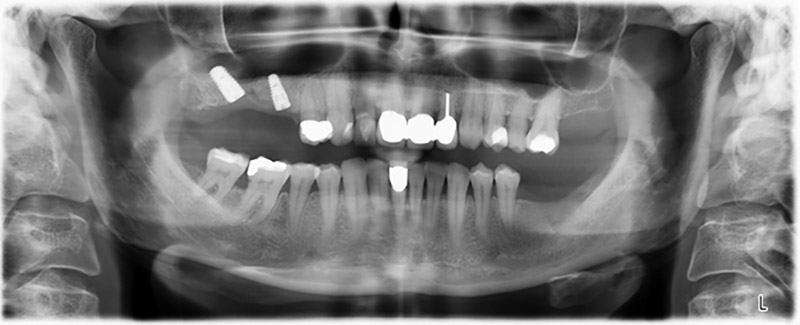

Orthopantomogram

Image 20: Orthopantomogram after treatment

Sky implants supplied by bredent were implanted – tooth 16: 5.5 x 10mm and tooth 14: 4.0 x 10 mm.